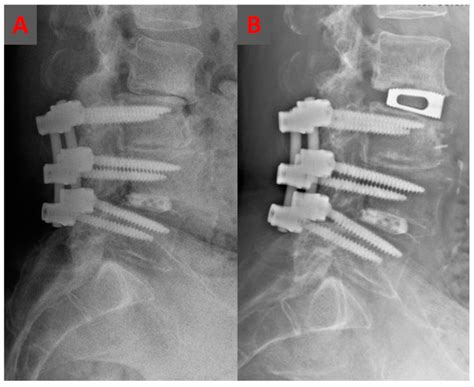

Pedicle Screws and Rods

Pedicle screws are placed into the pedicles of the vertebrae and connected by rods. This system provides rigid stabilization and promotes fusion. Pedicle screws and rods can be used in both open and minimally invasive procedures.

Interbody Cages

Interbody cages are placed between the vertebrae to maintain disc height and promote fusion. Cages can be made from materials such as titanium, polyethylene, or PEEK (polyether ether ketone). Cages can be used in conjunction with pedicle screws and rods for additional stability.